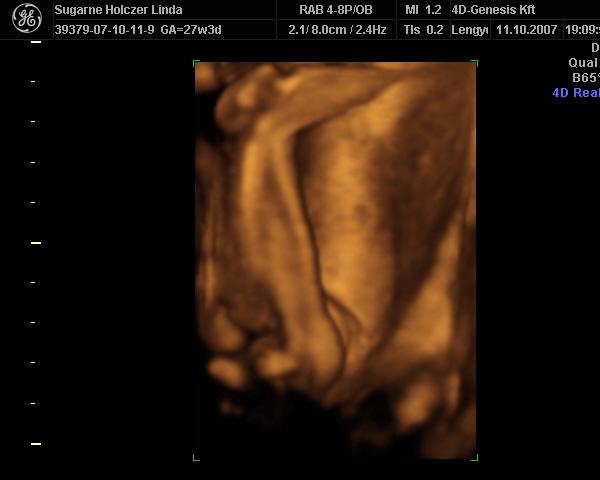

Ind, gyönyörű babád van

– köszi a képeket

Azt még megkérdezem, hogy ti most tulajdonképpen mennyi idősök vagytok? – a kép szerint 27hét+3nap, a vonalzód szerint pedig 26 hét.... – nagyobb a babád, mint kellene?